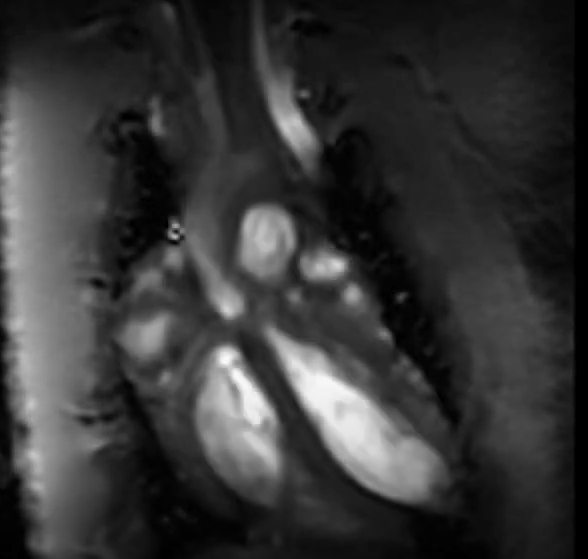

Exemples d'images acquises par notre IRM 7T